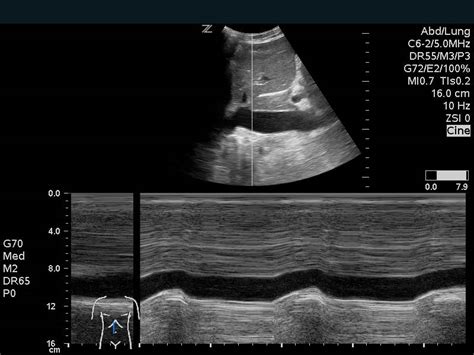

Alright guys, let’s start with the basics. Cardiac CT of the coronary arteries is basically a fancy way of saying we’re taking detailed X-ray pictures of the blood vessels that supply your heart muscle. Think of your coronary arteries as the vital highways that deliver oxygen-rich blood to your hardworking heart. When these highways get narrowed or blocked, it can lead to serious problems like chest pain (angina) or even a heart attack. This CT scan uses a special X-ray machine that rotates around your body, taking hundreds of cross-sectional images. A computer then stitches these images together to create incredibly detailed 3D pictures of your heart and its arteries. It’s non-invasive , meaning no surgery or insertion of tubes is involved, which is a huge plus. We can see the size and shape of your arteries, check for calcium buildup (a sign of atherosclerosis), and spot any plaque that might be narrowing the passageway. This gives doctors a really clear picture of your coronary artery disease risk and severity. It’s a powerful diagnostic tool that allows for early detection and intervention, potentially saving lives and improving the quality of life for countless individuals. The technology has advanced so much that these scans are now faster, provide higher resolution images, and require lower radiation doses than ever before, making them a safer and more effective option for many patients. It’s truly a marvel of modern medicine, offering a window into the intricate workings of our most vital organ without the need for invasive procedures, which is fantastic news for patients and healthcare providers alike. We can visualize the entire coronary tree, from the main branches to the smaller vessels, giving us a comprehensive view of the heart’s blood supply system. This detailed anatomical information is crucial for accurate diagnosis and treatment planning, ensuring that patients receive the most appropriate care tailored to their specific condition. It’s like having a high-definition map of your heart’s circulatory system, allowing for precise identification of any potential roadblocks or abnormalities.

So, why go through the trouble of getting this scan? Early detection is the name of the game, my friends. If those coronary arteries are starting to get a bit clogged up with plaque, a Cardiac CT can spot it way before you might even feel any symptoms. Catching atherosclerosis early means we can start treatments like lifestyle changes, medications, or other interventions to prevent those dangerous blockages from worsening. It helps doctors figure out the cause of chest pain or shortness of breath, differentiating it from other conditions. This reduces the need for more invasive tests in many cases, saving time, money, and patient discomfort. It’s all about being proactive with your heart health. This proactive approach is key to preventing major cardiac events. Imagine catching a tiny crack in a bridge before it becomes a major structural failure – that’s what an early Cardiac CT can do for your heart. It empowers both patients and doctors with crucial information to make informed decisions about managing cardiovascular health. We’re not just looking for problems; we’re also assessing the overall health and structure of the heart muscle itself, looking for things like hypertrophy (thickening of the heart muscle) or evidence of previous silent heart attacks. The ability to visualize calcification is particularly valuable, as the amount and location of coronary artery calcium is a strong predictor of future cardiovascular events. This information can help stratify risk more accurately and guide decisions about starting preventative therapies, even in asymptomatic individuals. It’s a powerful tool for personalized medicine, allowing us to tailor preventative strategies based on an individual’s unique risk profile. The precision of these scans means that we can identify even subtle changes that might be missed by other imaging techniques, ensuring that no stone is left unturned in the quest for optimal heart health. It truly represents a significant leap forward in our ability to diagnose and manage heart disease, offering hope and better outcomes for patients worldwide. The non-invasive nature also means a quicker recovery time and a significantly reduced risk of complications compared to more traditional diagnostic methods, making it a preferred choice for many healthcare professionals and their patients.